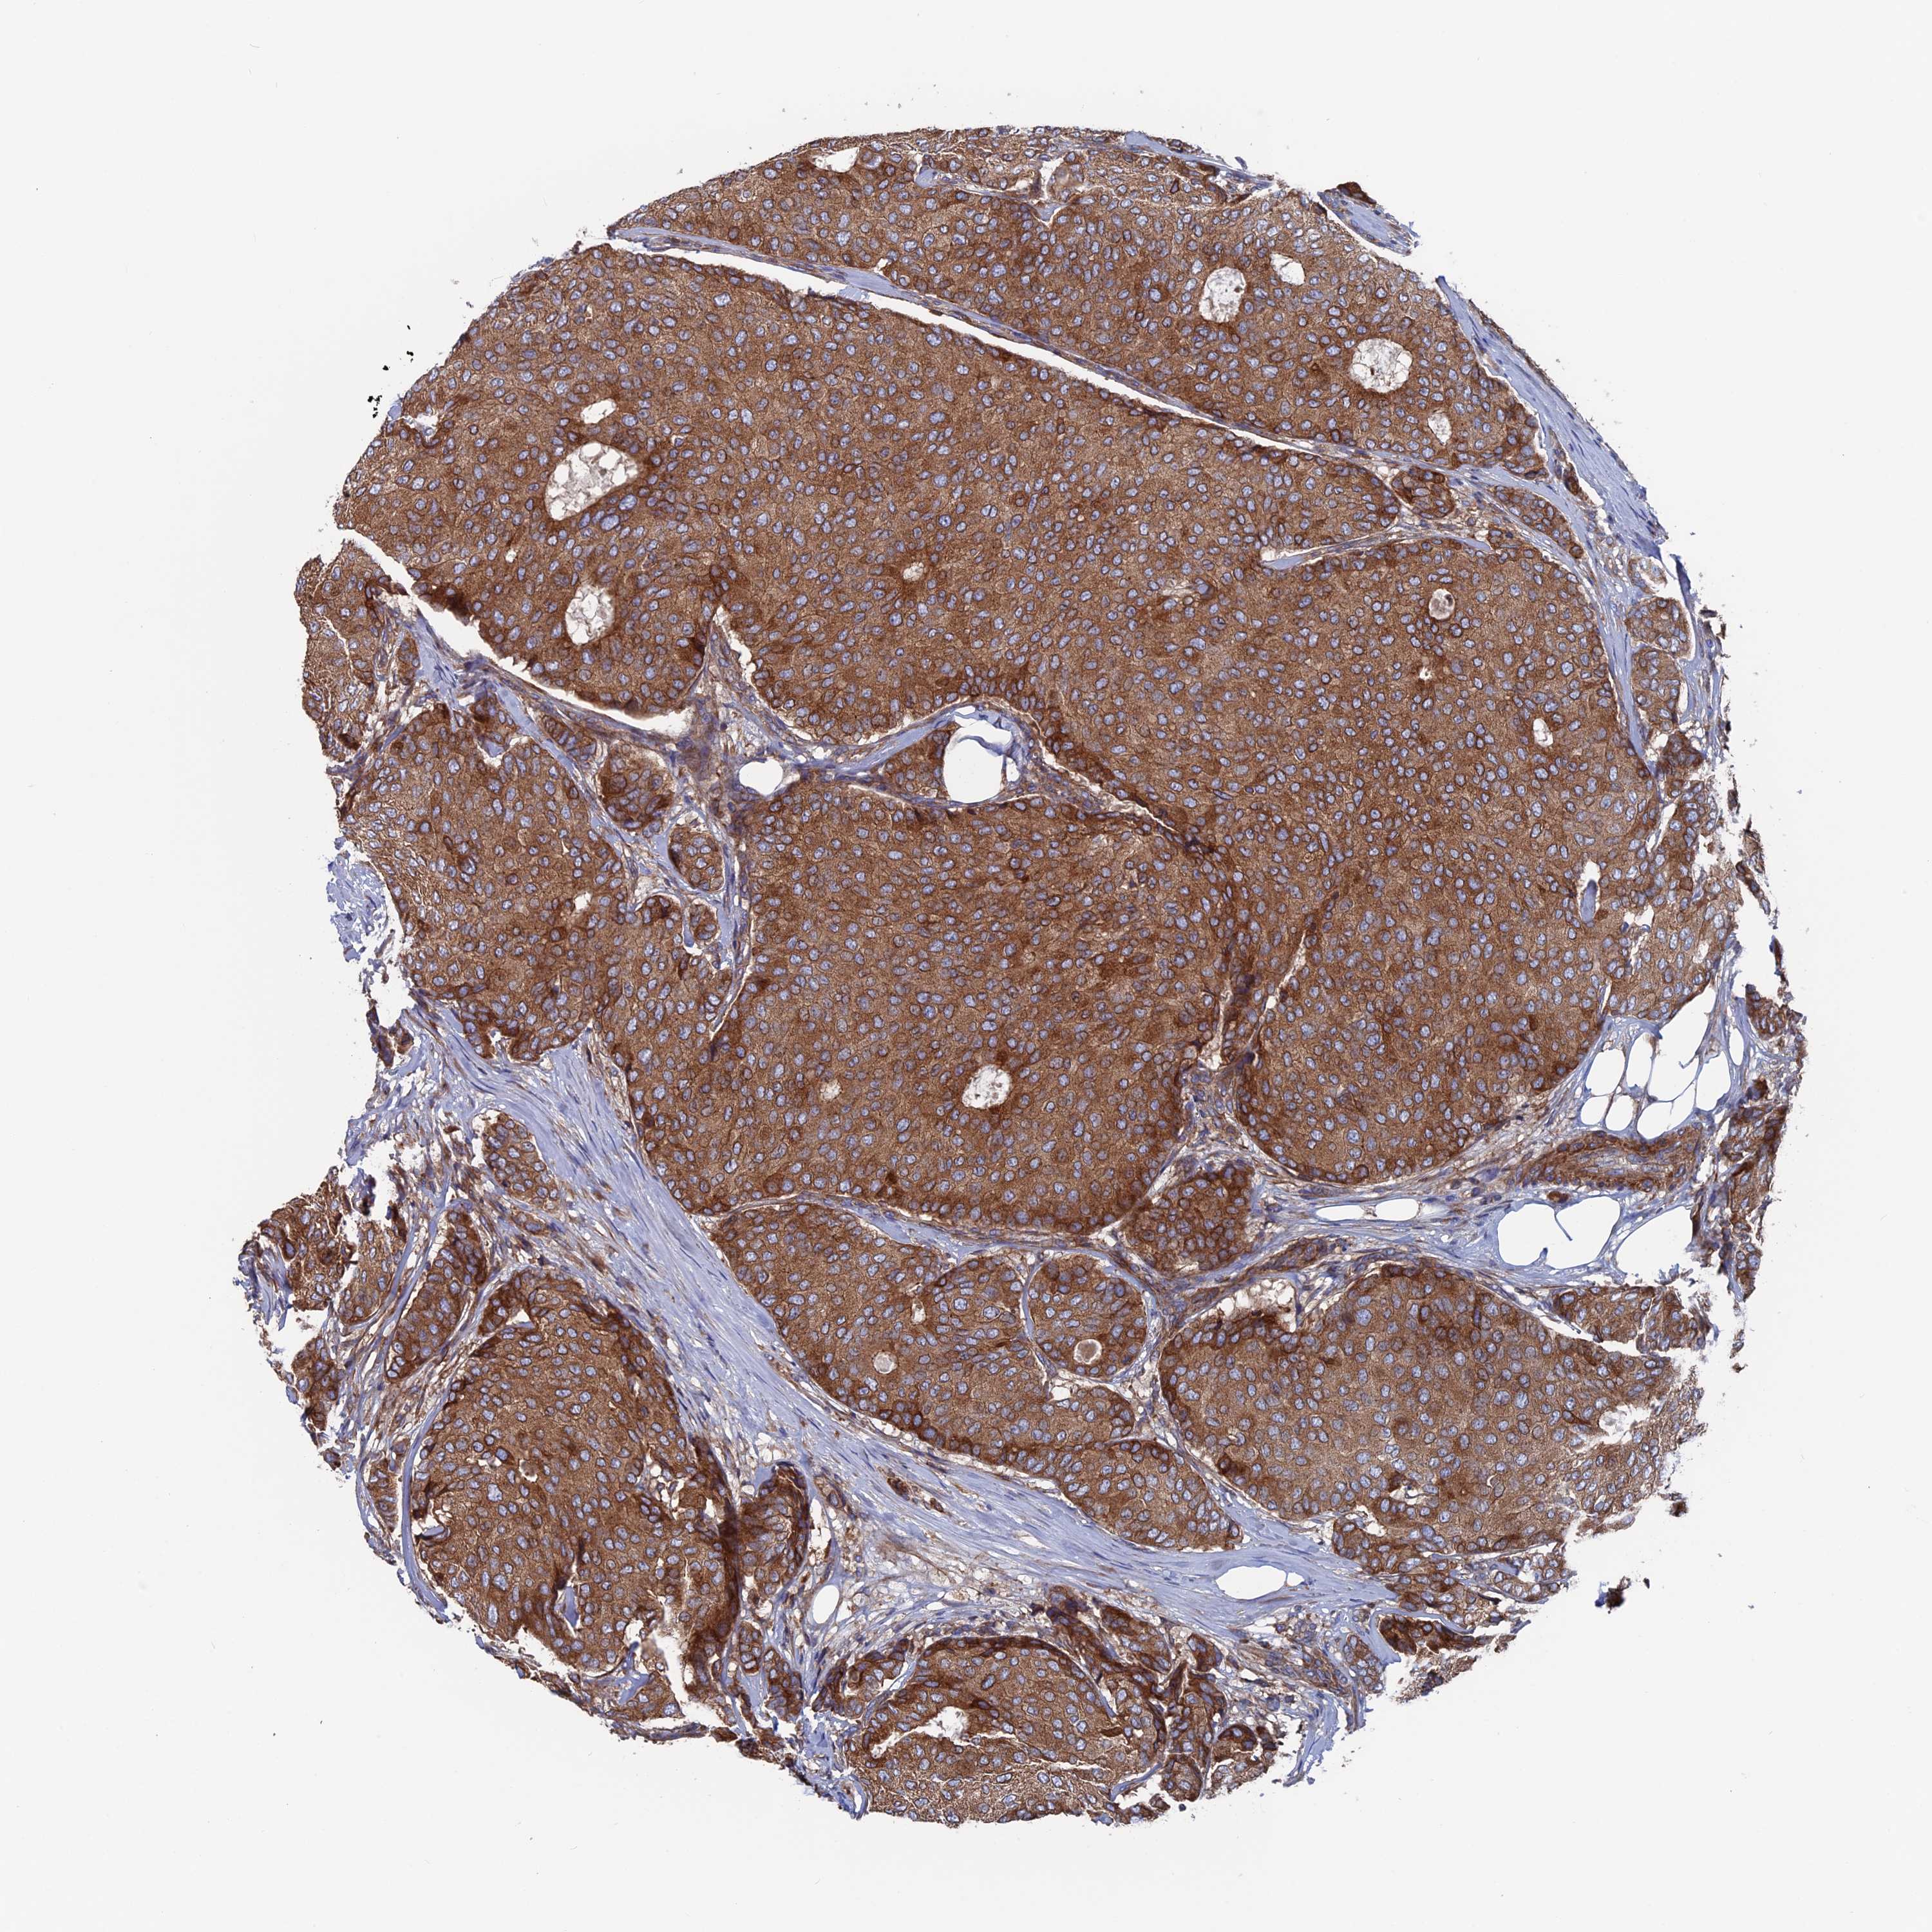

CANCER BREAST CANCER Show tissue menu

BRCA TCGA BRCA VALIDATION PROTEIN EXPRESSION